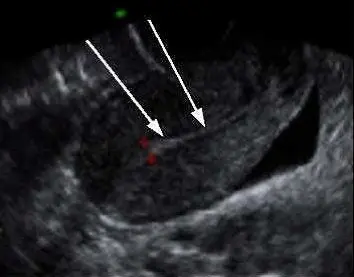

附圖為子宮超音波掃描,箭號所指的構造最可能為那一項?

本圖為經腹部骨盆腔超音波(Transabdominal pelvic ultrasound)的子宮矢狀切面(Sagittal view)影像:

- 影像方位與周邊構造:畫面右下側可見一呈現無回音(Anechoic)的黑色液體區域,此為充滿尿液的膀胱(Urinary bladder)。在經腹部超音波中,脹尿的膀胱被用來作為音窗(Acoustic window),以推開腸道氣體並利於觀察其後方的子宮。

- 子宮主體:位於膀胱後方的梨形實質器官。其外圍呈現均勻中等回音(Mid-gray echogenicity)的寬厚區域為子宮肌層(Myometrium)。

- 箭頭所指構造:兩條白色箭頭共同指向子宮正中央的一條細長、呈現高回音(Hyperechoic,較白)的線狀構造。此特徵為子宮內膜線(Endometrial stripe/echo),代表子宮腔前後壁內膜相貼合的介面。根據其細而單一的高回音線狀外觀,反映出此時內膜較薄,推測可能處於月經週期的早期增殖期